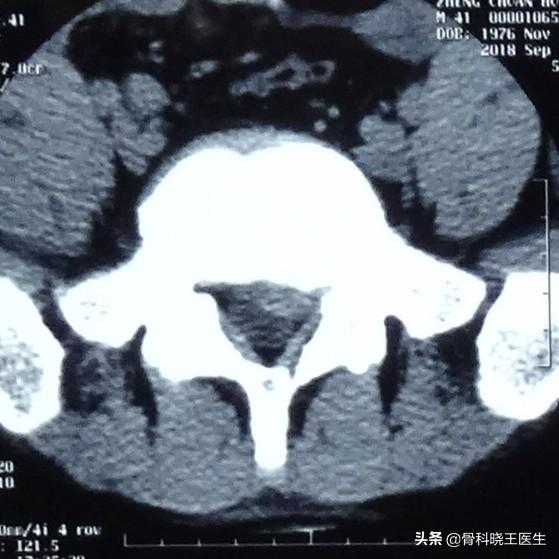

De nombreux patients et amis se posent la question suivante : la hernie discale lombaire peut-elle se résorber d'elle-même ? En fait, une fois que le disque lombaire est sorti, il est très difficile de revenir en arrière, ce qui est déterminé par la structure du disque lombaire. Le disque lombaire est situé entre les deux vertèbres lombaires adjacentes du corps humain et se compose d'un anneau fibreux externe et du noyau pulpeux au centre. Une hernie discale lombaire signifie que le noyau pulpeux traverse l'anneau fibreux qui l'entoure et fait saillie vers l'extérieur. Par conséquent, si une hernie discale lombaire se produit, cela signifie que la structure de l'anneau fibreux autour du disque lombaire a été endommagée, qu'elle est entrelacée et complexe, qu'elle n'est pas irriguée par le sang et qu'elle a une faible capacité de cicatrisation ; une fois détruite, il n'y a aucun moyen de la ramener à son état d'origine, et même si elle est à peine cicatrisée, la résistance sera bien pire. Si le nucleus pulposus ne traverse pas complètement l'anneau fibreux, il est possible de rétracter partiellement la hernie discale par manipulation osseuse et traction, mais tant que le nucleus pulposus continue à faire saillie lorsqu'on lui applique du poids, il y a très peu de chances qu'il reste rétracté pendant une longue période. En outre, comme l'anneau fibreux est divisé en plusieurs couches, il arrive que le nucleus pulposus soit déjà coincé dans l'anneau fibreux de différentes couches, ce qui est également difficile à rétracter. Par conséquent, au lieu de réfléchir à la manière de le rétracter, nous devrions réfléchir à la manière d'arrêter d'aggraver la hernie.

Les lésions discales sont généralement classées dans les catégories suivantes : bombement, hernie, prolapsus ou disque libre, avec un degré de gravité croissant.

Le traitement des patients souffrant d'une hernie, il est déjà nécessaire d'envisager la possibilité d'une intervention chirurgicale, mais ce n'est pas une mesure nécessaire, elle doit être déterminée par les données d'imagerie du patient combinées à l'histoire et aux symptômes, après tout, la région lombaire est un endroit plus grave, une fois qu'une lésion grave se produit, le lieu d'influence le plus commun est les membres inférieurs, les membres inférieurs auront des degrés variables de douleur, d'engourdissement.